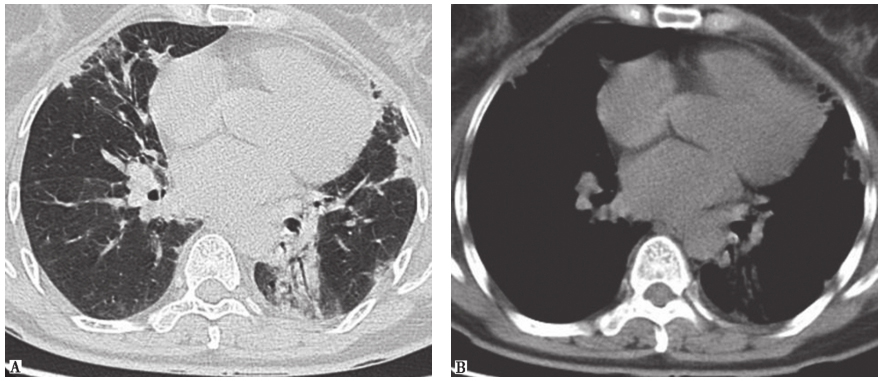

(3)脱屑性间质性肺炎(DIP):是间质性肺炎的一种类型,是以气腔单核细胞浸润为特征的慢性肺部炎症。病变的主要部位在细支气管及周围的气腔,其发病机制与外源性致病因子吸入和吸烟关系密切,因此与呼吸性细支气管炎伴间质性肺疾病及肺朗格汉斯细胞组织细胞增生症一起归为吸烟相关的间质性肺疾病。DIP的病理学特征为肺泡腔弥漫性分布均一的肺泡巨噬细胞。最常见的临床表现为进行性加重的活动后气促及呼吸困难,查体双下肺有吸气末Velcro啰音。支气管肺泡灌洗液(bronchoalveolar lavage fluid,BALF)中可见各类细胞(中性粒细胞、嗜酸性粒细胞、淋巴细胞,尤其是肺泡巨噬细胞)总数明显增多。BALF中见大量褐色素性肺泡巨噬细胞可协助诊断。典型HRCT表现为以中下肺为主的磨玻璃影,随着病情进一步发展,可表现为肺底部和胸膜下网格影、不规则条索影,结节影和蜂窝影比较少见(图3)。DIP的治疗主要是立即戒烟(部分患者戒烟后病情可自行缓解),其次是尽早应用糖皮质激素。

图3DIP胸部CT表现

男性患者,59岁,吸烟,咳嗽2个月余,临床诊断为DIP。胸部CT可见双肺弥漫性磨玻璃影